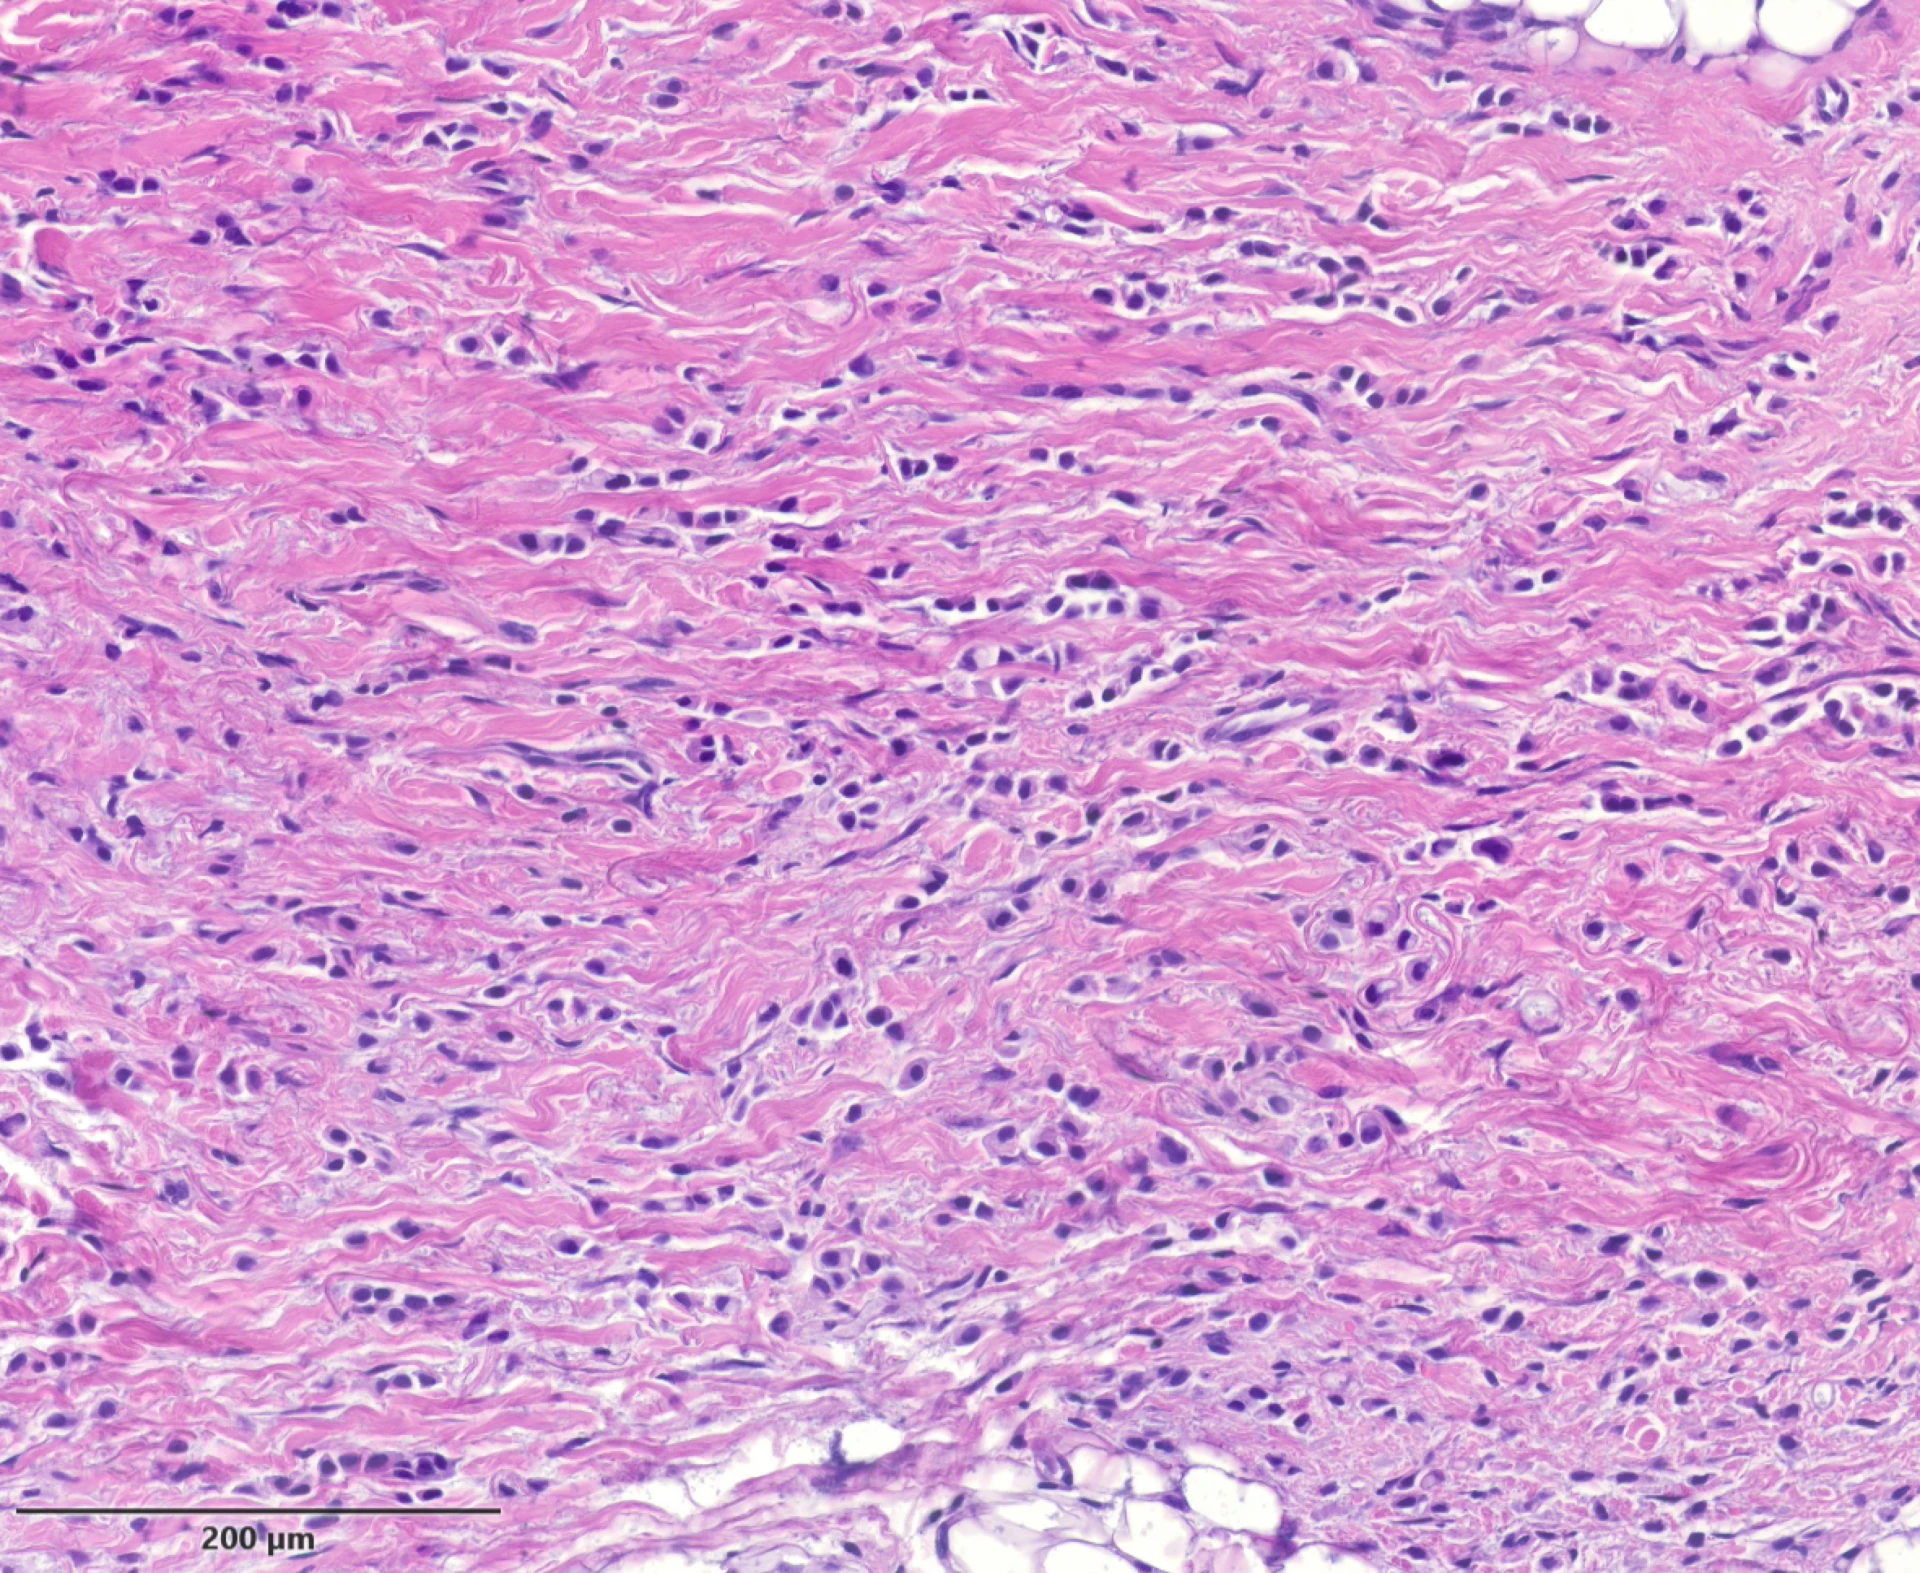

Die Standardfärbung der konventionellen Histologie ist die Hämatoxylin-Eosin Färbung (HE). In Abhängigkeit von der klinischen Fragestellung werden weitere Spezialfärbungen oder (enzym)histochemische Reaktionen, wie zum Beispiel PAS, Alcianblau, EvG, Gomori, Ziehl-Neelsen, Kongorot, Eisen. Mit deren Hilfe werden bestimmte Gewebestrukturen, aber auch Sekretionsprodukte, Substanzablagerungen, Pigmente oder Mikroorganismen sichtbar. Unser Labor beherrscht eine große Zahl an Sonderfärbungen für spezielle klinische Fragestellungen.